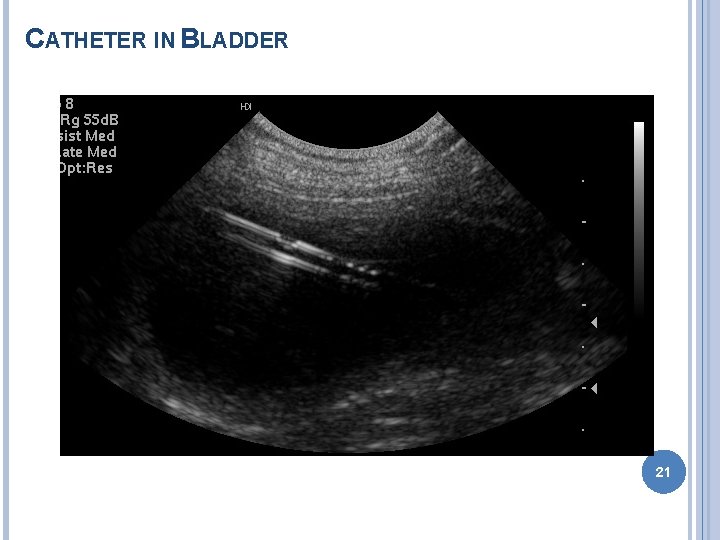

CATHETER IN BLADDER 21